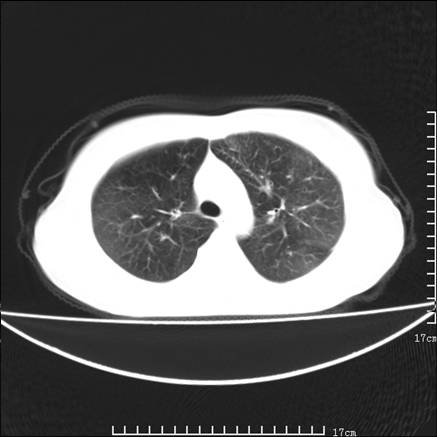

女,46岁,患胃溃疡多年,溃疡大小约1.0cm左右,后于5年前手术,病理为胃癌。主诉:半月前感冒后胸闷,气短,有咳嗽,无明显咳痰,无发热。偶有腰背部不适。

以下为高分辨扫描图像

双肺小叶间增厚,双肺散布粟米影和磨玻璃状影,以双肺上叶为重。结合病史考虑转移(癌性淋巴细管炎)可能性大。

结合病史:认为是典型肺部癌性淋巴管炎、淋巴结转移。请看图解。

正如caihe主任所言,影像表现结合临床病史应该支持肺癌性淋巴管炎;上肺大片边缘不清的渗出病变,多系感染所致,临床有感冒病史并咳嗽表现。肺癌性淋巴管炎临床一般无咳嗽、咳痰症状。

肺癌性淋巴管炎征象分为主要征象及合并征象,主要征象包括:

1、近肺门支气管血管周围间质结节状增厚;

2、小叶间隔结节状增厚;

3、小叶中央间质结节状增厚;

4、胸膜下间质结节状增厚。

合并征象为:纵隔淋巴结增大,胸腔积液,肺多发随机分布的小结节等。